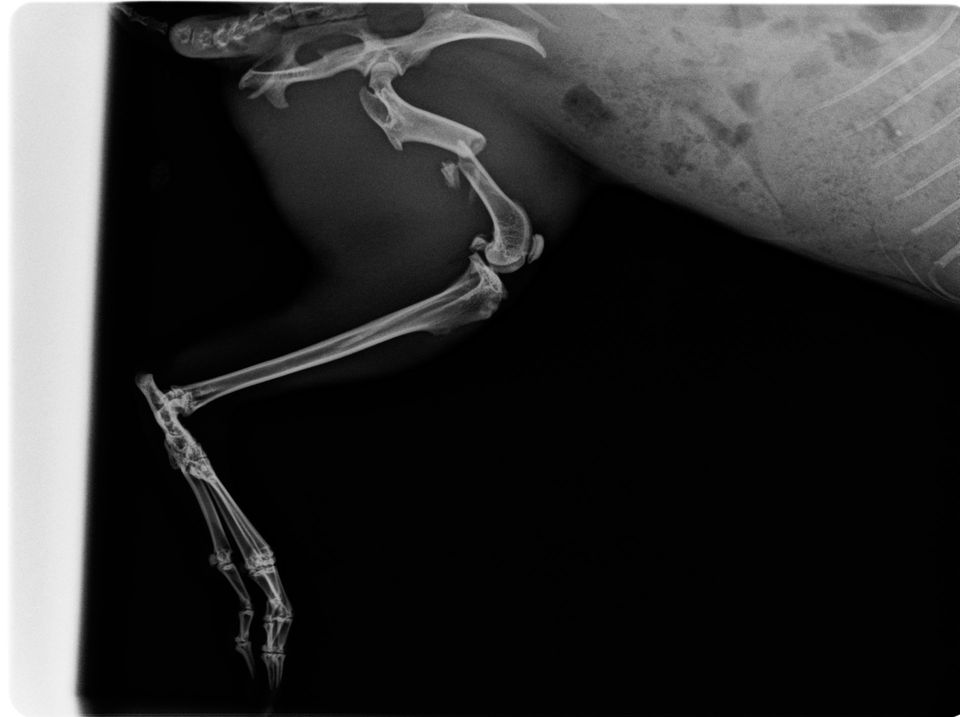

Schulter: Osteochondrosis dissecans (OCD)

Ellbogen: Ellbogengelenksdysplasie, isolierter/ fragmentierter Proc. coronoideus (ICP), isolierter Proc. anconaeus (IPA), Luxationen

- Frakturbehandlung:

z.B. Osteosynthese mit Drahtspickung, Zuggurtung, Fixateur externe, Schrauben, Plattenosteosynthese.

Statt den herkömmlichen Implantaten setzten wir bei der operativen Versorgung von Knochenbrüchen neue, winkelstabile Titan-Platten ein. Diese gewährleisten eine bessere Verbindung zwischen Platte und Knochen, liegen dem Knochen nicht mehr unmittelbar auf und erlauben somit kleinere Implantate. Dabei werden die Blutgefäße geschont und eine schnellere Heilung gefördert.